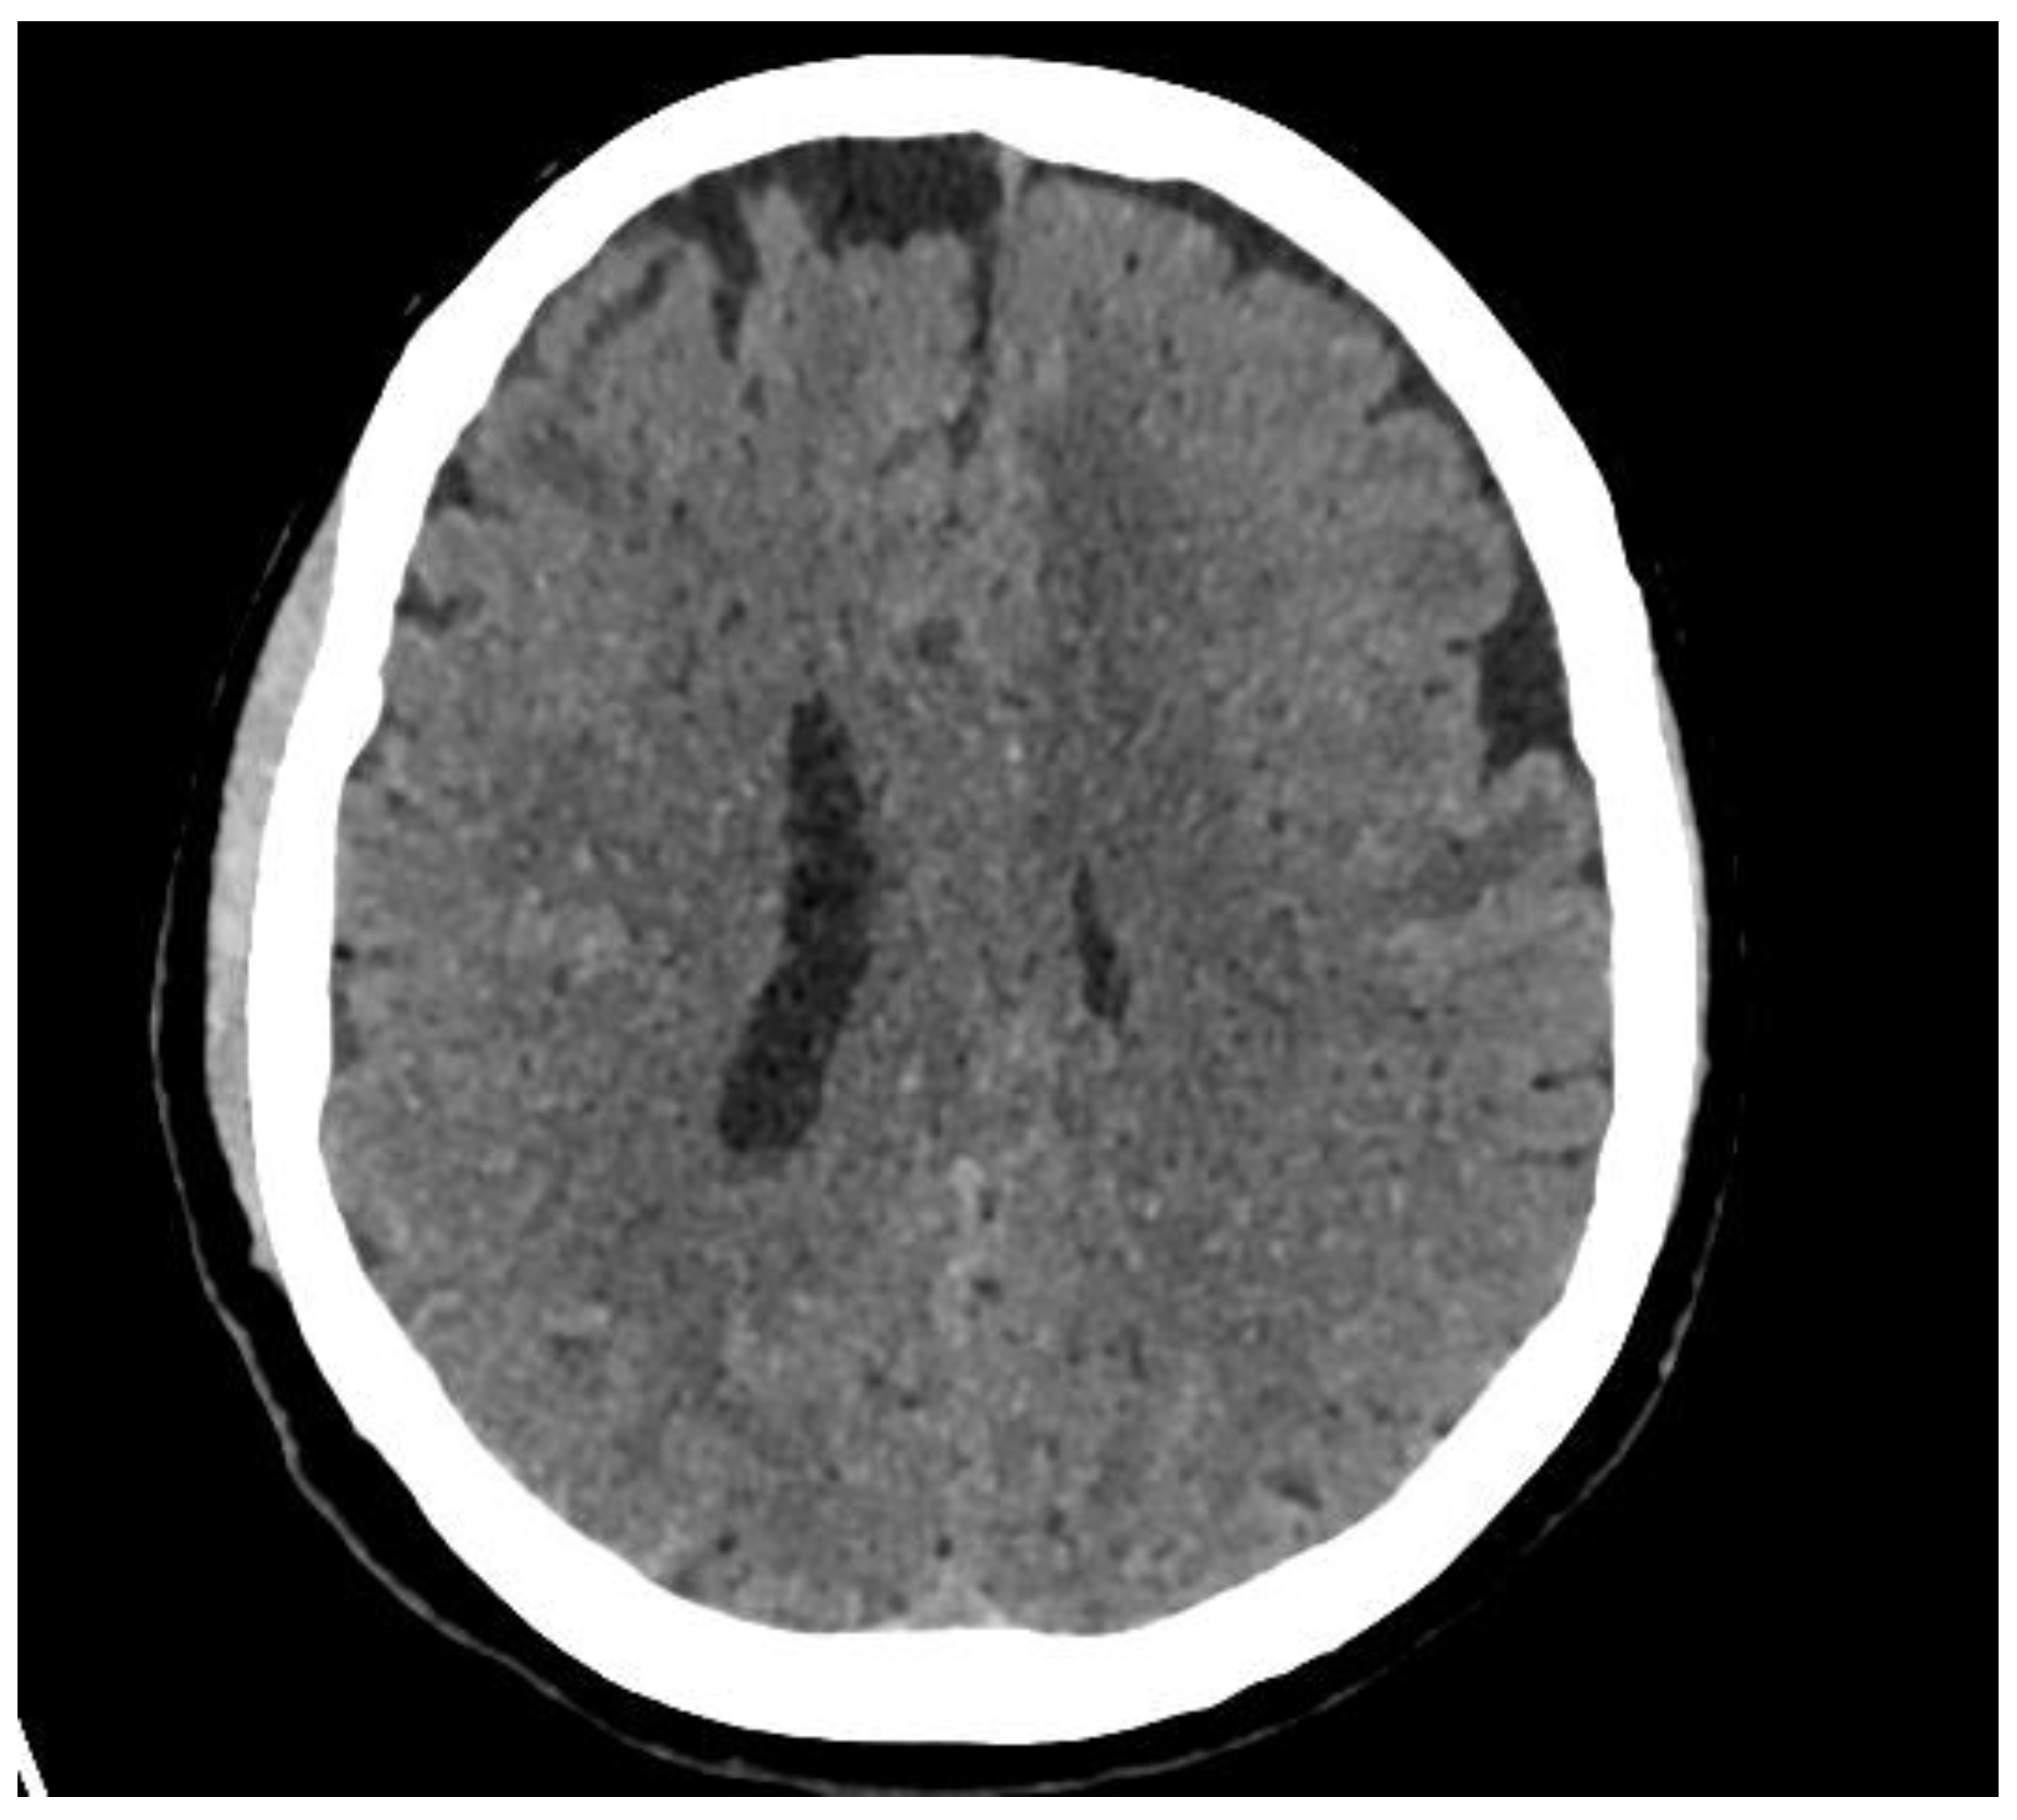

A Diagnostic Dilemma of White Matter Lesions and Cerebral Oedema without Identifiable Cause—A Neurological Conundrum

2. Case Report